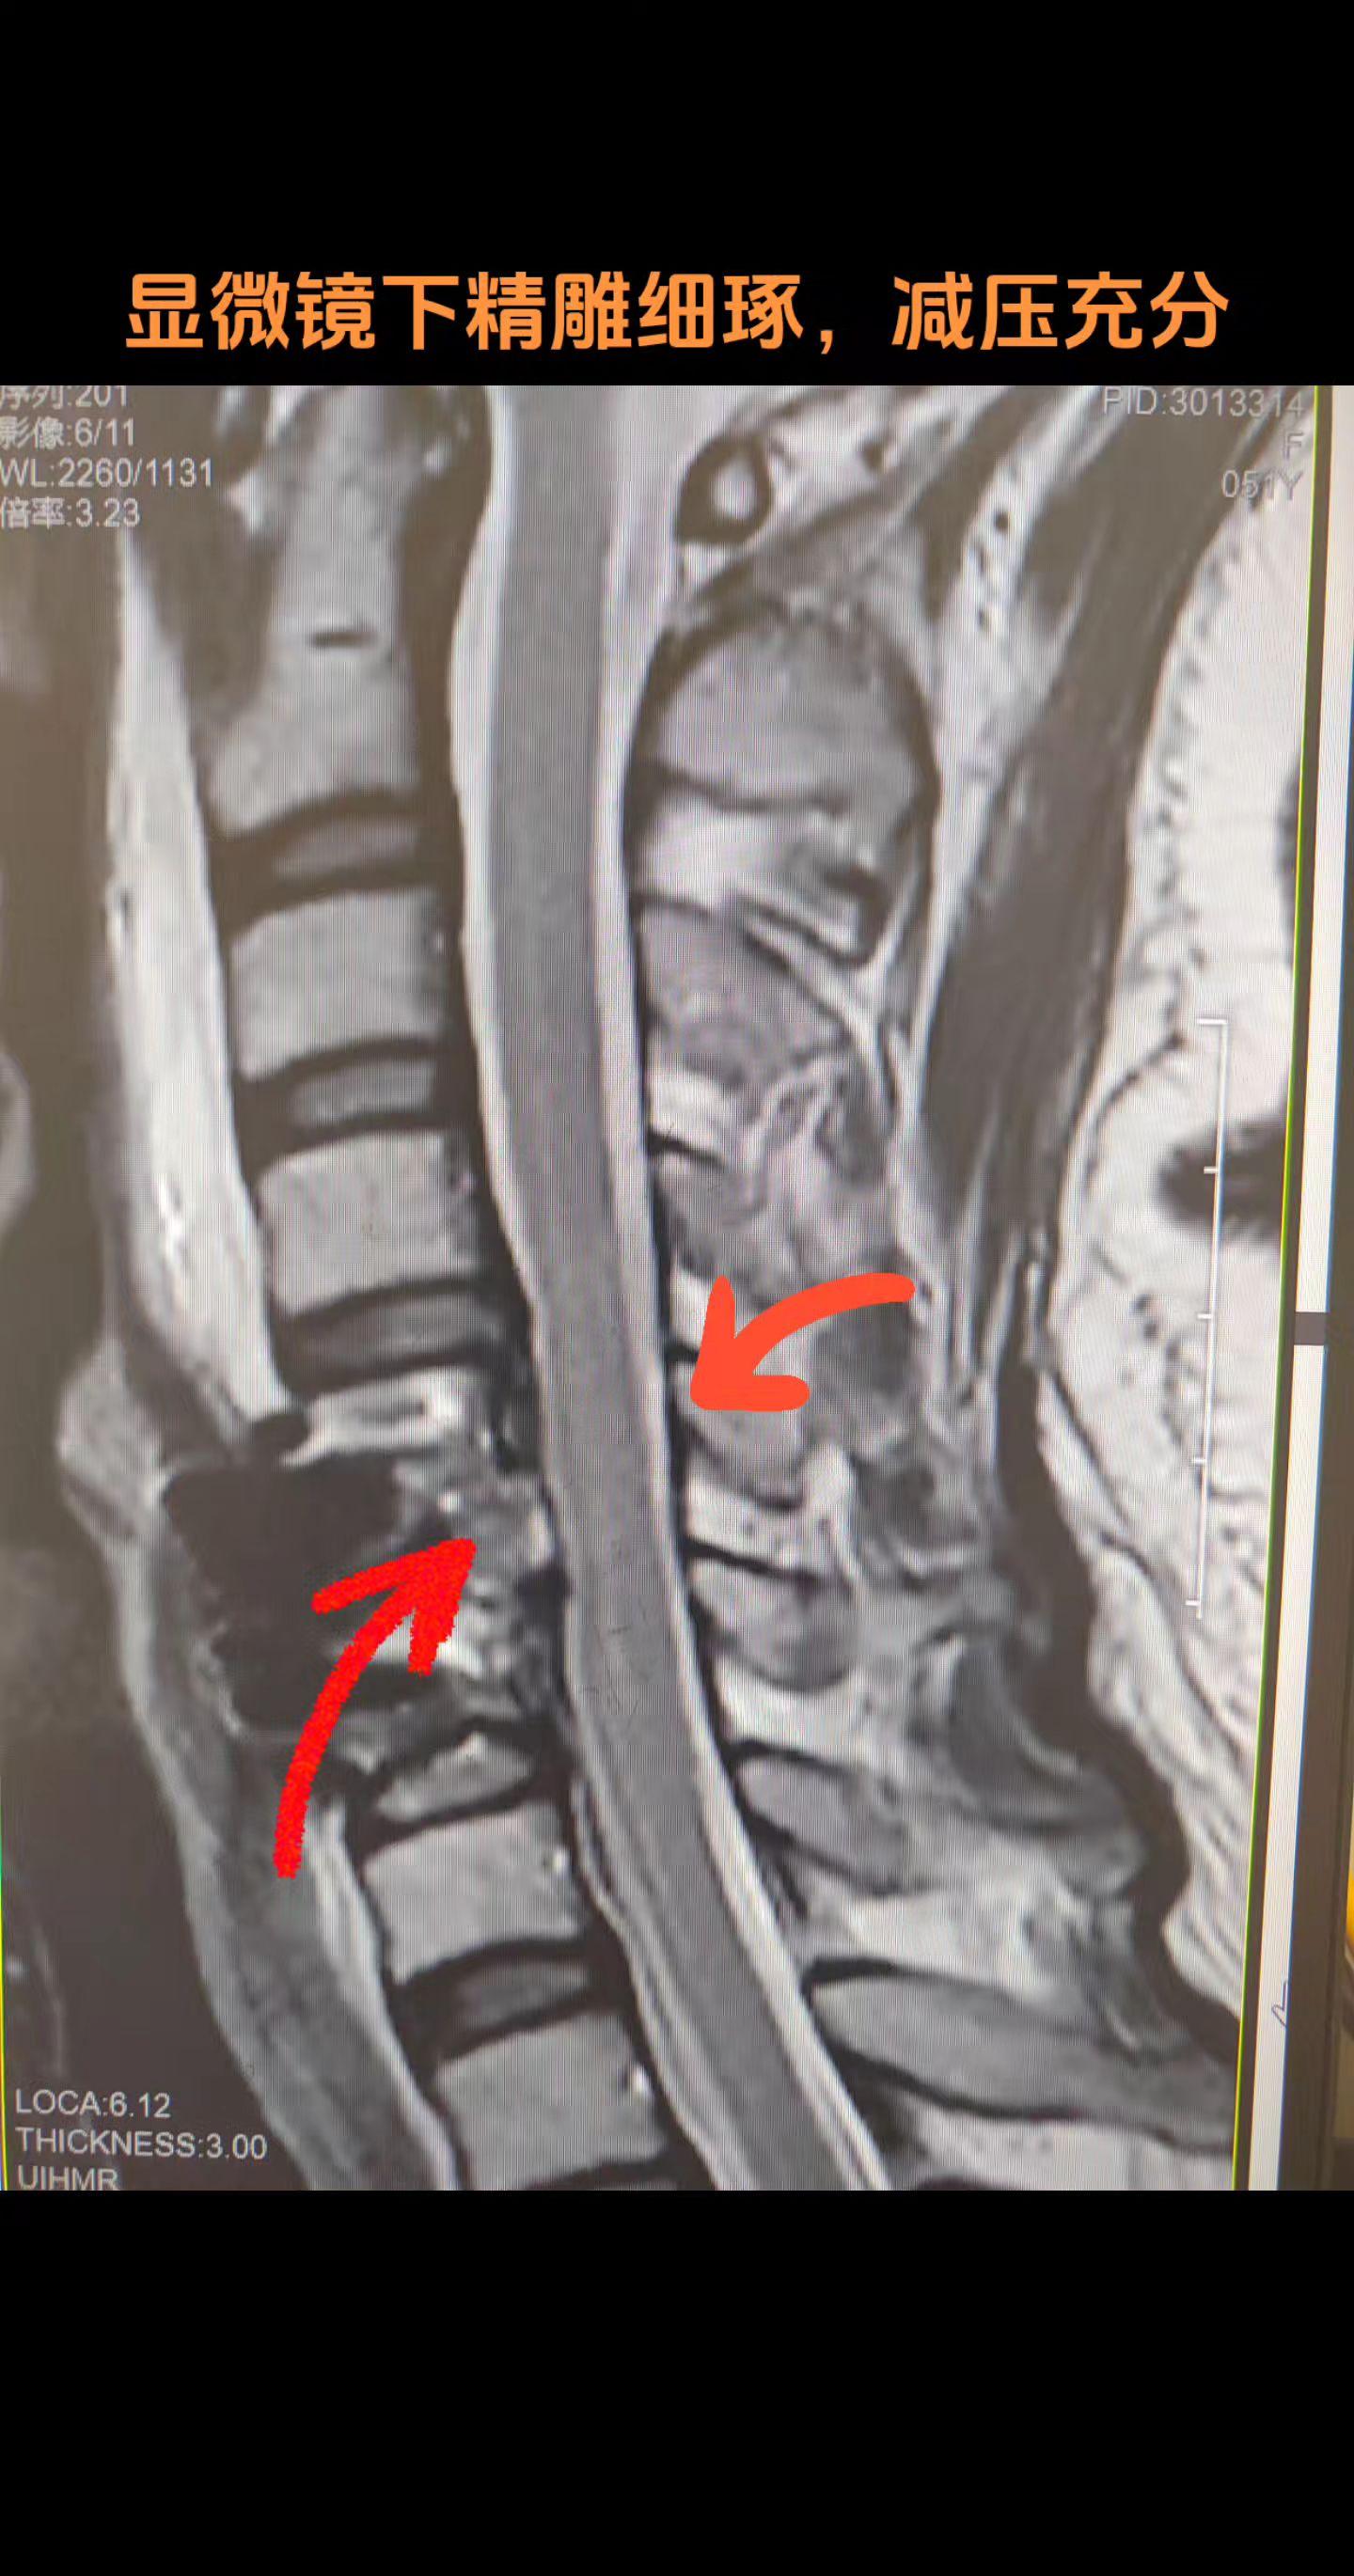

颈椎病手术前后对比。蚂蚁啃骨头